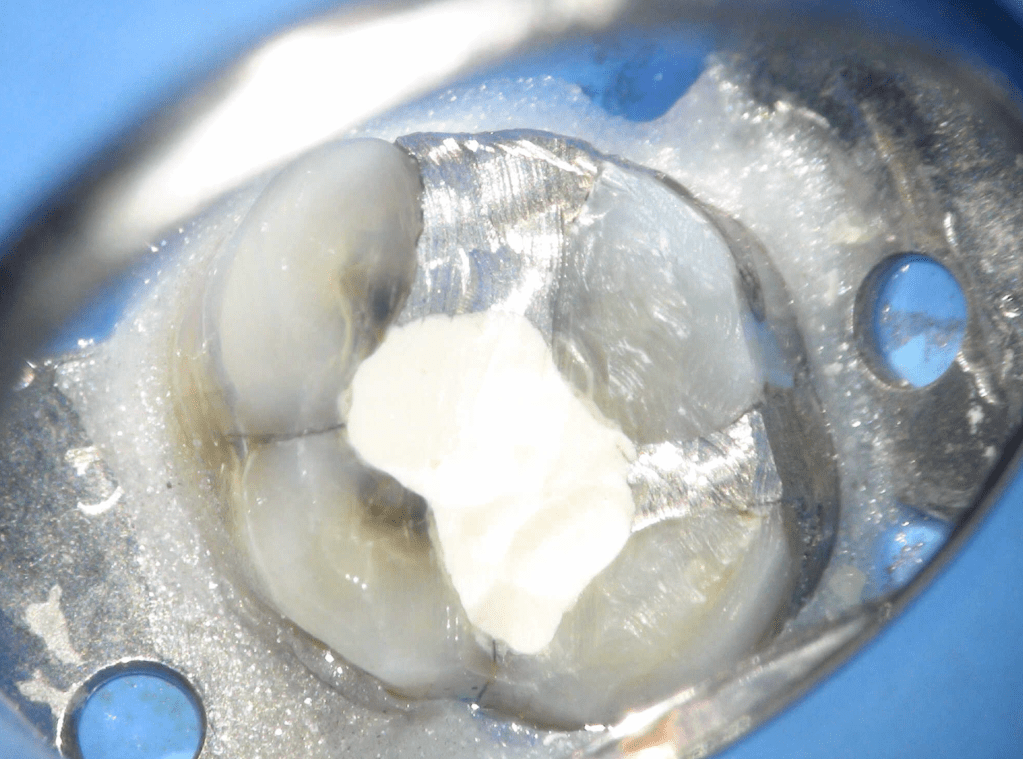

Fisura, remoción amalgama para explorar